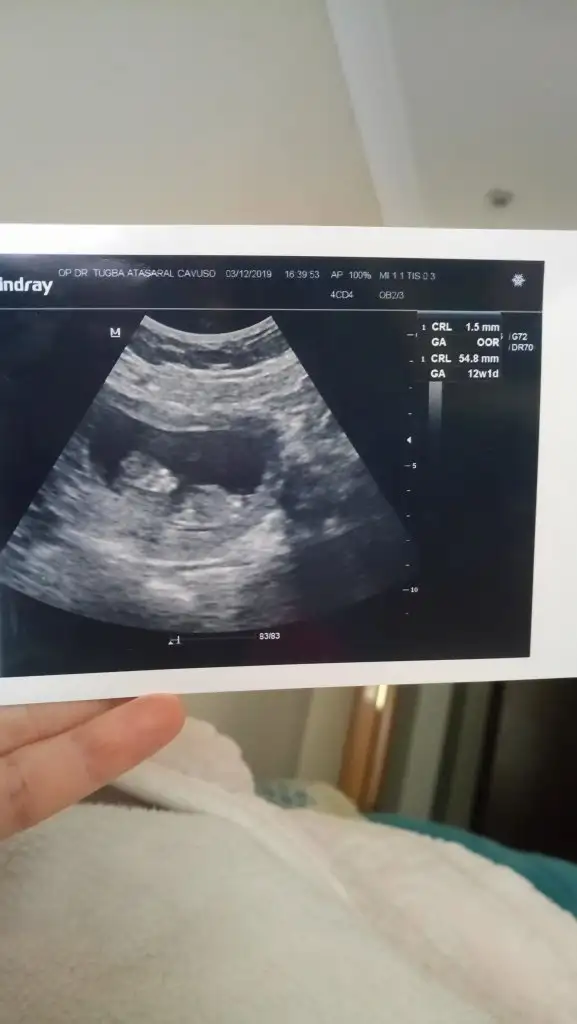

MasaAllah erken demis ne guzel. Ben de haftaya gidicem belki tahmin ederBenim 12, hafta doktor erkek gibi görünüyor dedi ama tabi değişebilir

Önceki gebeligimde doktor 12.haftada erkek demişti doğru çıkmıştı, erkekler erken belli ediyor.Benim 12, hafta doktor erkek gibi görünüyor dedi ama tabi değişebilir

Cinsiyet belli degıl demı daha dedım , cok merak edıyosan yuzde 50 ıhtımalle soylıyım dedi ,güldük :)) bellı degılmış canım erken dahaCanim dun gittin demek cinsiyat tahmini yapmadi dimii? Erken demistir gerci